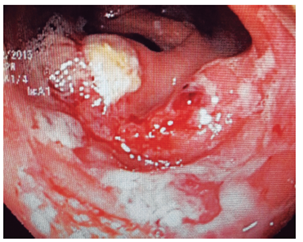

Varios estudios han demostrado la utilidad de los procedimientos endoscópicos en este contexto. Se debe aclarar que no hay un patrón endoscópico típico de infección por oportunistas, por tanto, siempre se deben tomar biopsias. Se sugiere que la infección por Salmonella predomina en el colon derecho y va desde un eritema hasta ulceraciones. La infección por amebas suele afectar el ciego y rectosigmoide, con ulceraciones y zonas de necrosis (Figura 4 ). El CMV puede generar ulceraciones que predominan en el colon izquierdo (Figura 5 ). El rendimiento de la colonoscopia va desde el 27% al 39%, y el CMV es el germen más común 38.